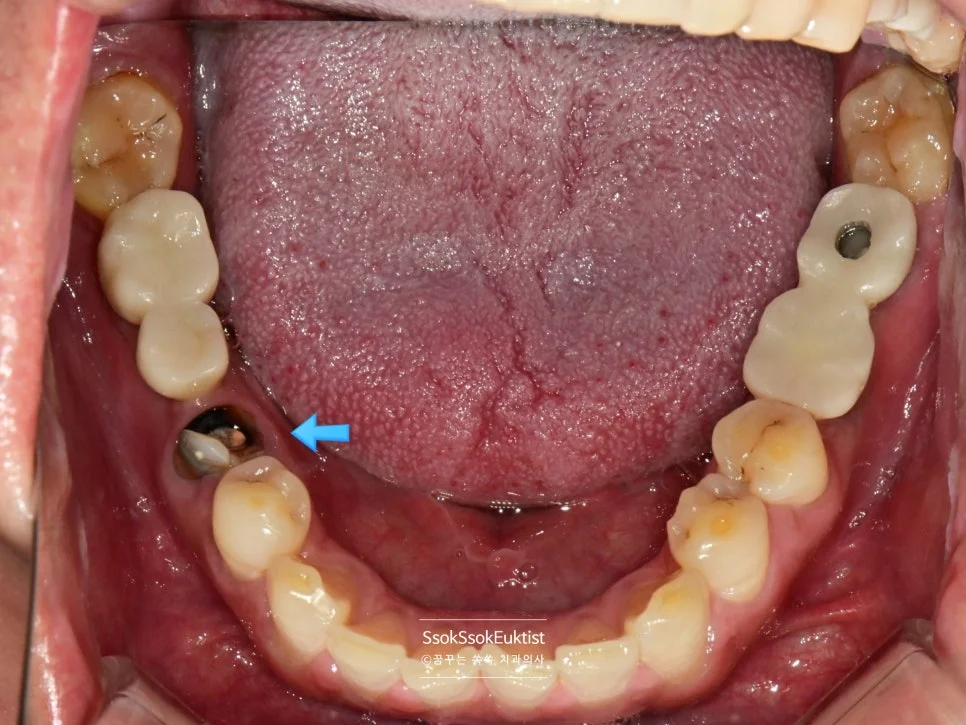

치료 전 정면 구내사진 — 다수의 치아 문제가 보이는 상태

사진에서 1번, 4번 치아의 경우 치아 머리가 너무 남지 않아 발치 후 임플란트가 필요한 상황입니다.

자연치아 살리기에 진심인 마곡나루 치과지만 모든 치아를 다 살려서 쓸 수는 없거든요.

1번, 4번 치아의 경우 자연치아 살리기 조건 중 세 번째 조건을 만족하지 못하여 발치의 대상입니다.

한편, 3번의 경우 치아를 발치하고 오랜 시간이 지난 위치로 예쁘게 임플란트 식립을 진행하면 됩니다.

그런데 2번의 임플란트를 한번 보면 뭔가 잇몸이 부자연스러운 것을 볼 수 있는데요.

임플란트 주변에 뼈가 다 녹아내리고 그 바깥에 잇몸까지 혈류를 받지 못해 점점 괴사하고 있는 모양새입니다.